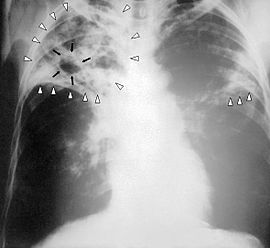

tubercolosi-vitamina-DNella lotta contro la tubercolosi la vitamina può giocare un ruolo fondamentale, accelerando il recupero nei pazienti.

La scoperta arriva dai ricercatori della Queen Mary University di Londra, lo studio, pubblicato sulla rivista Proceedings of the National Academy of Sciences, suggerisce di accreditare la pratica, in uso nel diciannovesimo secolo, di mandare i malati nei luoghi di villeggiatura per assorbire i raggi del sole.